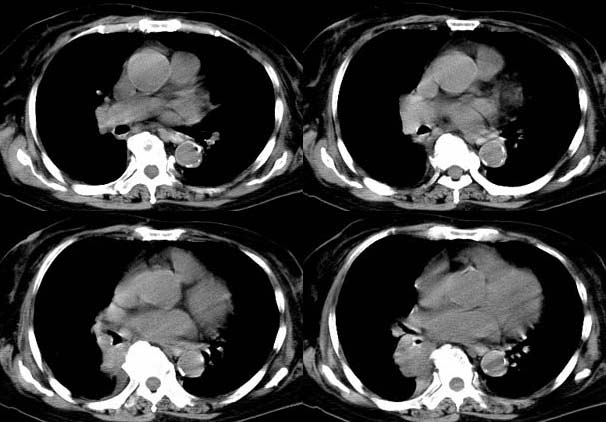

请大家讨论右下肺占位性质。ct值约35-55hu

右肺门后侧软组织肿块,内见点状钙化,年龄76,ct值约35-55hu ,考虑肺癌可能

右肺门后侧环绕支气管的软组织肿块,内见点状钙化,远端有阻塞性炎症,年龄76,ct值约35-55hu ,考虑右肺中心型肺癌。建议支气管镜鉴。

右下肺,右肺门后方见团块状软组织密度影,边缘呈分叶状,其内见斑点状钙化,肿块内部支气管腔闭塞。肿块后方可见胸膜尾征,外侧方见斑片状模糊阴影。右肺门淋巴结增大。

考虑:右侧中央型肺癌伴阻塞性肺炎及右肺门淋巴结转移